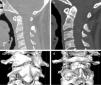

We present two cases of minimally invasive posterior transarticular screw fixation of C1-C2. The points for screw insertion were visualized by endoscopy via the instrumental port. A patient with a type III odontoid fracture with subluxation underwent a minimally invasive posterior stand-alone transarticular screw fixation. Despite the application of compression screws, for technical reasons, only minimal compression on the anterior third of the C1-C2 lateral joint was achieved. However, complete fracture fusion was achieved with stable fibrous C1-C2 fusion 2.5 years postoperatively. A second patient with a chronic type II odontoid fracture underwent percutaneous C1-C2 fixation by the same method. After 2 years, fracture fusion and C1-C2 lateral mass ankylosis were achieved. The use of a tubular retractor and endoscopy in stand-alone screw fixation of C1-C2 allows direct visualization of the screw entry point and decreases surgical trauma. This procedure might be an alternative to other methods of transarticular instrumentation.